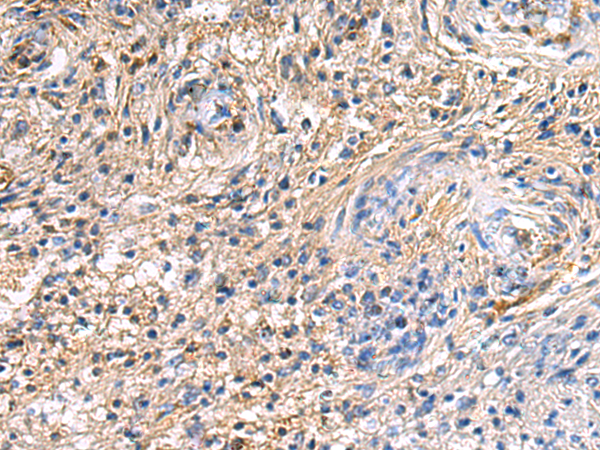

分类: 科研抗体货号: P10422别名: 3PK; MK-3; MDPT3; MAPKAP3; MAPKAP-K3; MAPKAPK-3应用: WB,IHC反应种属: Human, Mouse, Rat